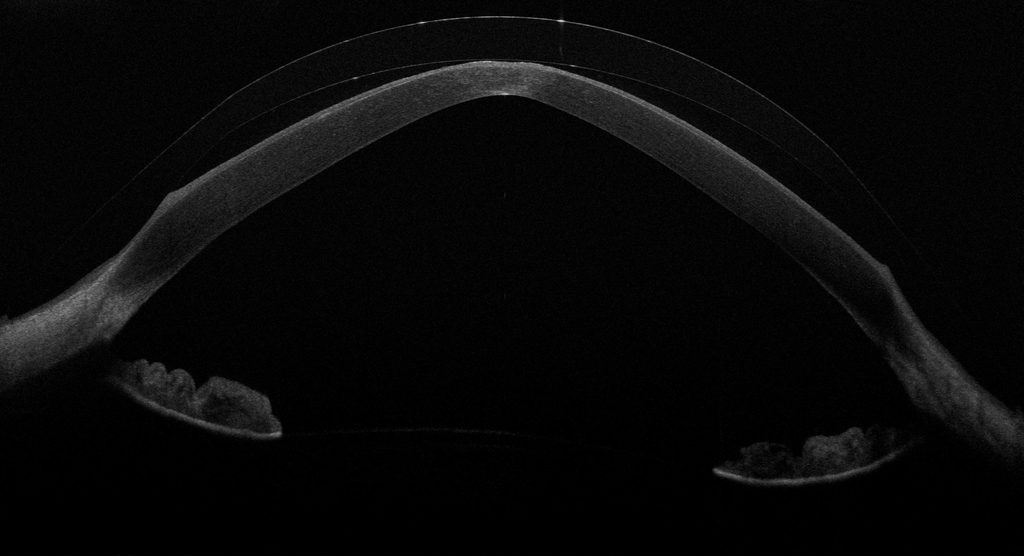

Das OCT – die Optische Kohärenztomographie – macht genau diese Befunde zugänglich. Es erzeugt einen hochauflösenden Querschnitt durch das vordere Auge: Linse, Tränenreservoir, Hornhaut – alles in einem Bild, im Mikrometerbereich aufgelöst.

In dieser OCT-Aufnahme sehen Sie eine Sklerallinse mit ausreichender Clearance. Der obere Bogen ist die Linse, der untere die Hornhaut. Der schwarze Raum dazwischen ist das Tränenreservoir – gut gefüllt, gleichmäßig verteilt. So soll es aussehen.